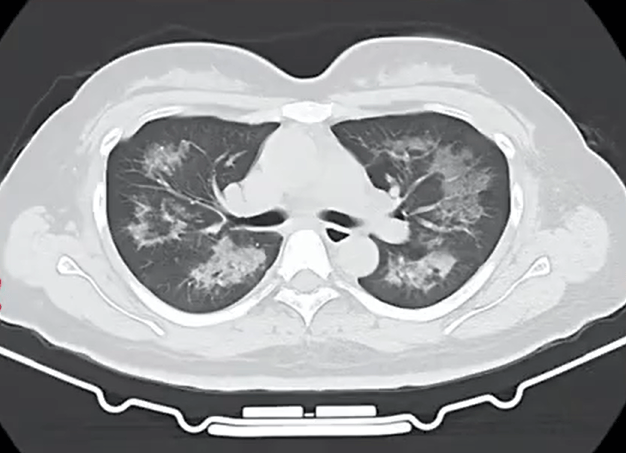

胸部CT进一步显示,她的双肺出现多发斑片状模糊影,被诊断为间质性肺炎貔貅盘虚拟币。医生判断,病因很可能与她近期长期接触的某类物质相关。经过医生反复细致地询问病史,小江才说出自己存在长期、频繁使用定妆喷雾的情况。